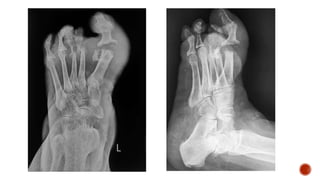

 Dorsoplantar radiograph of the foot shows destruction of the head of the 5th

metatarsal and the base of the proximal phalanx of the 5th toe with apparant

widening of teh joint space.

 Foot radiograph :

 Dorsoplantar: metatarsals in neutral position

 Medial: DP projection with the foot angled 30-40° medially

 Lateral

 Weight bearing